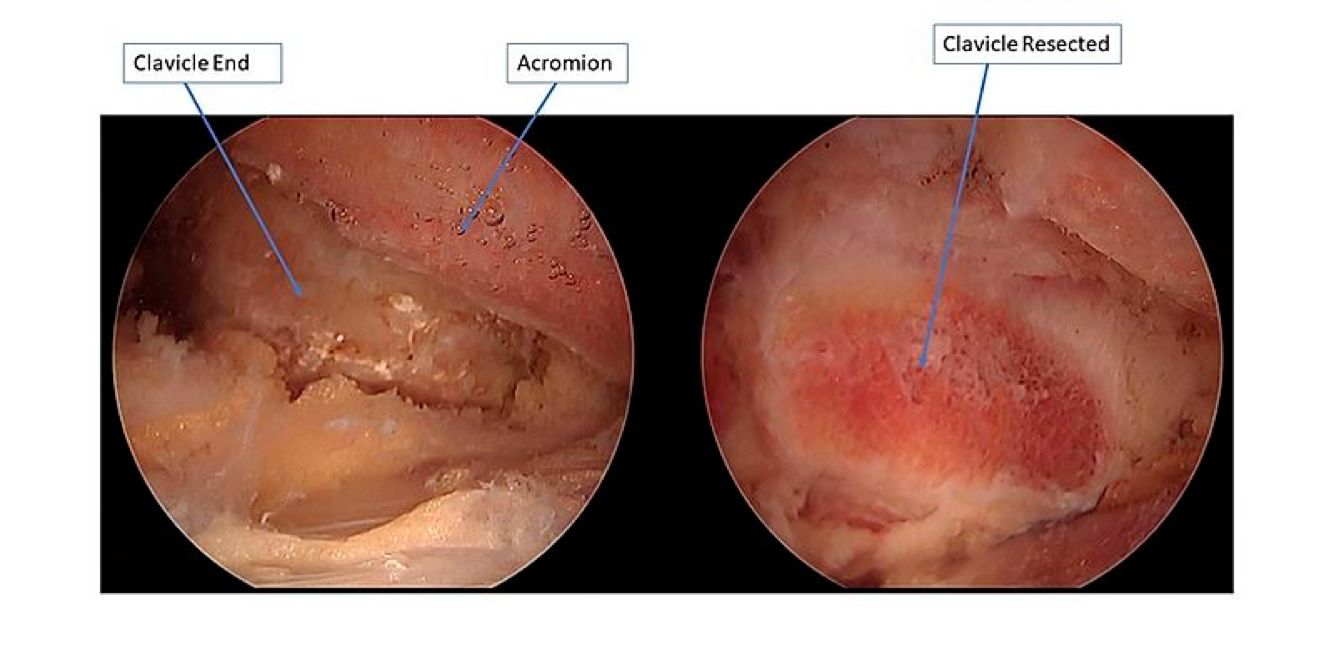

Distal clavicle or "AC" (acromioclavicular) arthritis results in pain over the shoulder, especially right on top of the shoulder with overhead and cross body maneuvers. Sometimes pain from AC arthritis can be present in addition to rotator cuff pain or a completely separate issue. Pain from the AC joint is usually quite distinct from rotator cuff pain but they can be confused. Arthritis of the AC joint is initially treated with physical therapy, NSAIDs, and cortisone injections. When these measures fail to help, a limited distal clavicle resection surgery can be performed to open up the space between the clavicle and acromion. This can be performed arthroscopically and requires only a few days of immobilization afterwards.

Shoulder radiographs demonstrating "AC" arthritis.

Arthroscopic images before and after distal clavicle resection, demonstrating an increased space between the distal arthritic clavicle and the acromion.